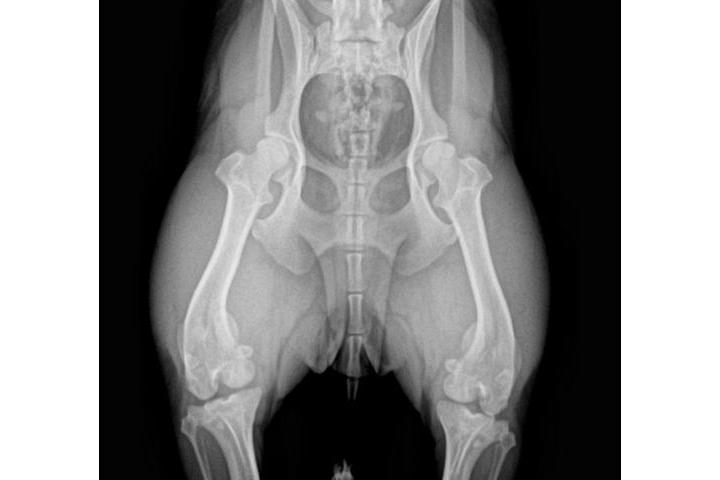

Actualisation sur la cause

Victoria Riera Serra

Teaming Manager

le 30/05/2017 à 17:52h

4a radio

Tengo buenas no tan buenas noticias...la adopción legal de Sólo se ha resuelto....ya es oficialmente nuestra....rstamos a la espera de la documentación para realizar el cambio de demarcación y censarla en Reus...por otro lado la visita al veterinario y las rx confirmaron el diagnóstico inicial...el grado de luxación de sus rótulas es muy grave y la cirugía es inevitable....estoy a la espera del informe del traumatólogo y del nuevo presupuesto para haceroslo llegar a todos; si bien es algo más económico que los dos anteriores sigue subiendo un pico. Habrá que operarprero una para y esperar para posteriormente operar la otra..de ese modo podrá llevar una vida relativamente normal hasta su total recuperación....la buena noticia es que no hay indicios de artrosis lo que significa que no hay dolor...una vez iniciado la primera intervención se valorará es estado de sus tendones para descartar un "tendón laxo"...a lo largo del día recibiré por mail el informe completo junto con una copia de las rx para poder mostraroslas....de nuevo gracias a todos por ayudarme a hacer posible el tratamiento de Snoopy